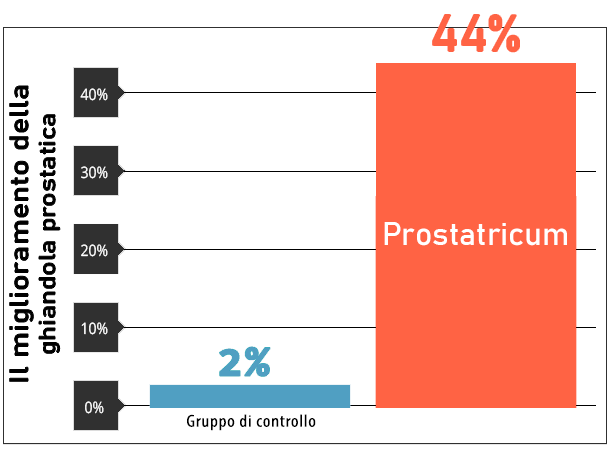

Gli studi confermano l'effetto

In un mese di ricerca, lo stato della ghiandola prostatica degli utilizzatori di Prostatricum è migliorato

del 44% rispetto al gruppo di controllo!